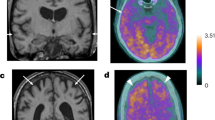

Among the two proteins that were associated to the future risk of AD, CDH6 and HAGH, the latter was not detected in the CSF in >90% of the subjects in ADC cohort. CSF CDH6 protein levels were not associated with AD (β = 0.329, SE = 0.220, P = 0.136) in the overall as well as in APOE stratified analysis (P > 0.114; see Supplementary Table 5). However, multiple regression analysis adjusted for age and sex revealed a significant association of CDH6 CSF levels with both p-tau (β = 23.2, SE = 3.4, P = 3.48 × 10−11) and t-tau (β = 207.4, SE = 36.4, P = 2.40 × 10−8) when pooling AD patients and controls (Table 3 and Fig. 3). In the APOE stratified analysis, levels of CDH6 were significantly associated with p-tau and t-tau levels but not with Aβ−42 levels in CSF in three APOE strata (see Table 3). When stratifying by case-control status (Supplementary Table 6), CDH6 levels were significantly associated with p-tau and t-tau levels in both cases and controls. In controls, also Aβ−42 was positively associated with CDH6 (P < 1 × 10−3; see Supplementary Table 6).

Association of CDH6 and HAGH protein levels with Aβ−42, p-tau, and t-tau in CSF